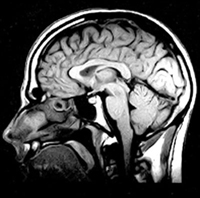

The journey from the first images of tubes of water to the installation of the first magnetic resonance imaging (MRI) scanner in a hospital required a huge amount of research and development both in the private and public sector, but it only took about 10 years. This involved mathematicians, physicists, engineers, computer scientists, biomedical scientists and medical practitioners in one of the best modern examples of “translational research”. It is estimated that in 2002 about 60 million MRI examinations were performed throughout the world. MRI has had a major impact on many aspects of clinical practice; probably most notably in neurology (Box 1b).

![]() b) Modern magnetic resonance sagittal section of a human head. |